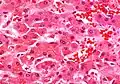

Micrograph showing a Mallory body. Original magnification 200X. H&E stain. Liver micrograph showing abundant Mallory bodies, as seen in alcohol use disorder.

Liver micrograph showing abundant Mallory bodies, as seen in alcohol use disorder. Mallory bodies in hepatocellular carcinoma. Trichrome stain.